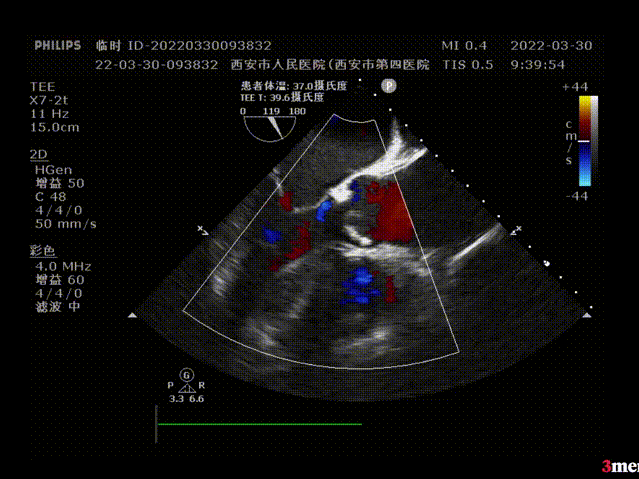

超声评估:

植入前超声评估:瓣叶开闭不良

植入后超声评估:瓣膜形态良好,无瓣周漏